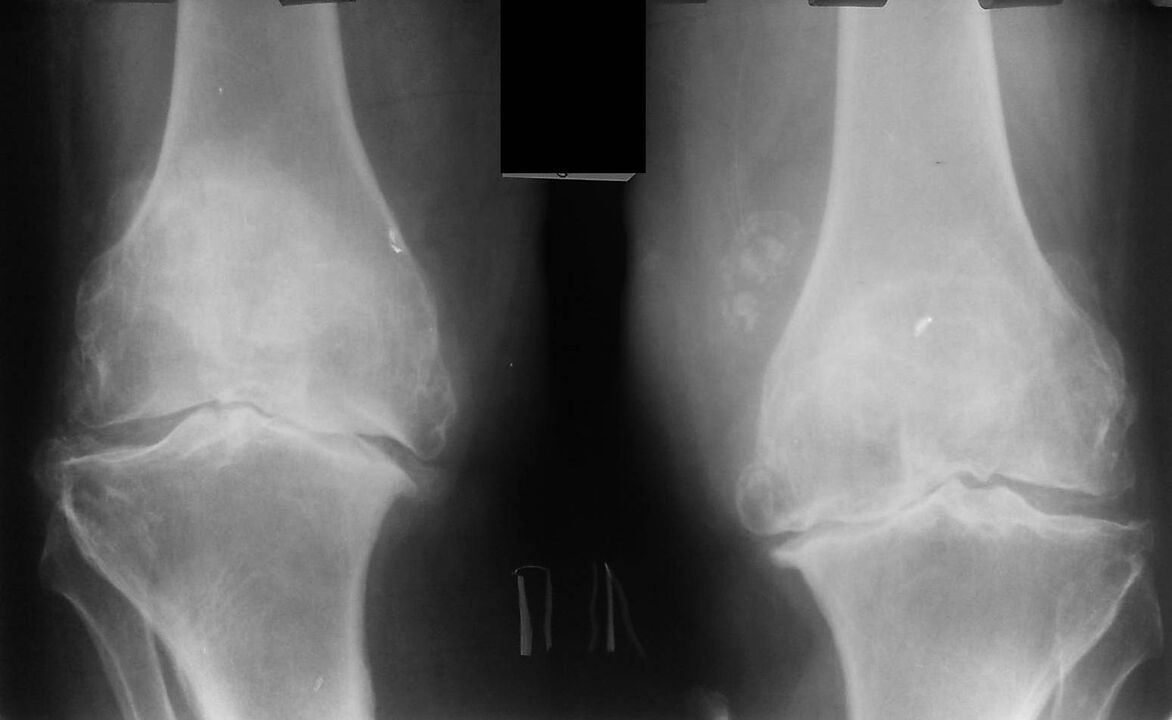

O spray Hondrox é un remedio para a dor nas articulacións. O medicamento úsase para tratar e previr a artrite, a osteoartrite e outras enfermidades articulares. O spray Hondrox ten unha composición natural, ten un forte efecto antiinflamatorio e rexenerativo, alivia a dor e o inchazo. Portugal recoñeceu a eficacia do spray Hondrox para o tratamento e prevención das articulacións, o produto pódese mercar no sitio web oficial e Braga é un dos lugares coa entrega do produto.